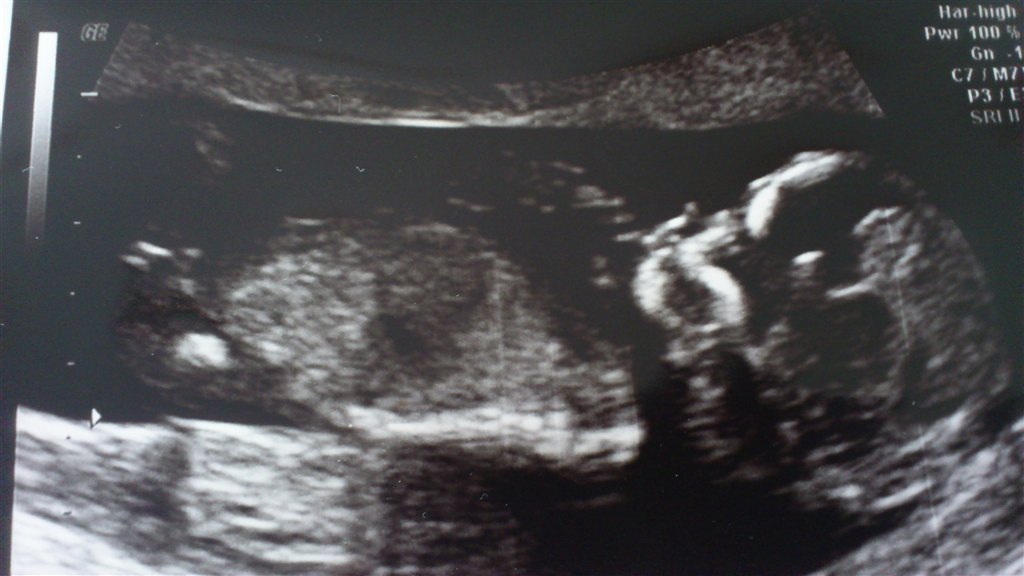

Jeg har en lille livlig krabat i maven, som slet ikke ville ligge stille i starten + det lignede den havde hikke! Den blev dog mere rolig og vi kunne se hjerte (inkl. 4 hjertekamre), blære, mavesæk, hjerne, arme, ben osv. og alt så normalt ud og som det skulle. Det var bare så stort, at se den lille for første gang

Risikotal 1:3640, så det er jo som det skal være.

Og så et lille billede også